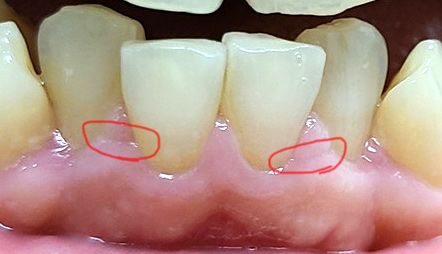

잇몸이 가로로 갈라지는건 왜 그런건가요?

이와 이 사이의 잇몸이 가로로 갈라지는 이유는 뭔가요?

잇몸 여기저기 이런 현상이 있고요.

간혹 심하게 갈라진 곳은 양치할때 아파요

사진 꼭 참조해주세요

잇몸병때문에 그런것 같습니다.

정확한 진료는 가까운 치과 방문해서 보시길 권유드립니다..